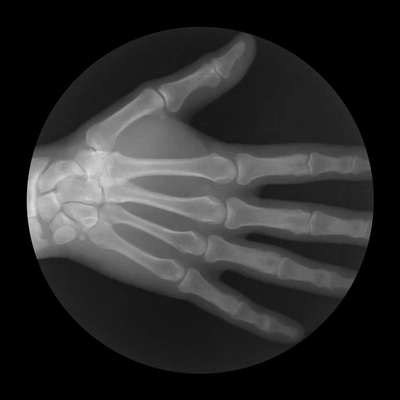

Οι κινήσεις των οστών αποκαλύπτουν τι συμβαίνει μέσα στο σώμα μας.

Οι παρακάτω φωτογραφίες, για την ακρίβεια πρόκειται για ακτινογραφίες του ορθοπεδικού Noah Weiss ο οποίος σε συνεργασία με τον φωτογράφο Cameron Drake, δημιούργησαν αυτές τις εκπληκτικές απεικονίσεις. Με τον τρόπο τους, ρίχνουν φως στο τι συμβαίνει στις αρθρώσεις.